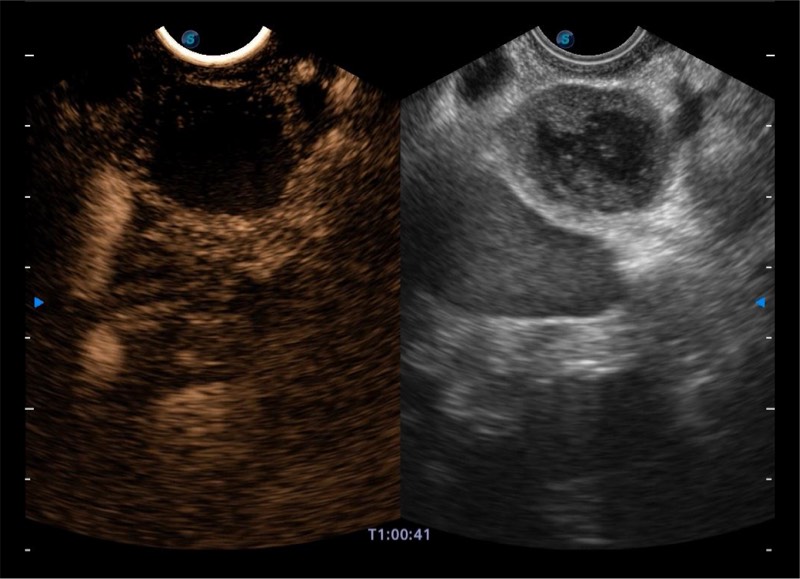

基于二十年的超声技术积累,哈哈体育官网提供了最新一代的独立超声主机,在提供高质量图像的同时满足多学科使用。具备常见多普勒技术并提供弹性成像、声学造影等高端影像技术。新一代传感器具有更强的抗干扰能力并减少图像伪影。

• 4-12MHZ宽频输出